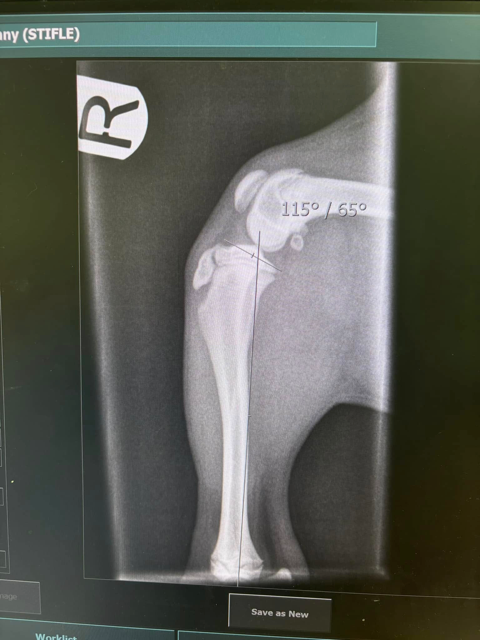

Tibial crest avulsion fracture

Tibial crest avulsion fracture and a fracture of the left proximal growth plate of the tibia (red arrows) with caudal shift of the proximal segment.  The caudal shift of the proximal segment created 9 degrees change of the tibial plateau angle (TPA). TPA 34 degrees left leg-abnormal,  TPA right leg 25 degrees-normal.

Anatomical reduction and normalizing TPA is desirable in this cases in order to reduce risks of early cruciate ligament rupture in future.

The fracture was anatomically reduced and stabilized with k-wires and tension band combined with cross pins technique.